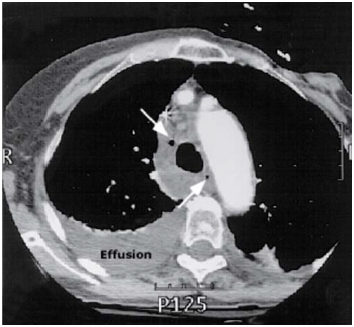

Um homem de 41 anos de idade apresentou dor torácica de início abrupto após libação alcoólica, seguida de vários episódios de vômitos. O estudo radiológico de tórax evidenciou derrame pleural à esquerda, sendo submetido a drenagem torácica com saída de líquido achocolatado e resíduos alimentares. Com base nessas informações, assinale a alternativa que designa a síndrome supracitada.